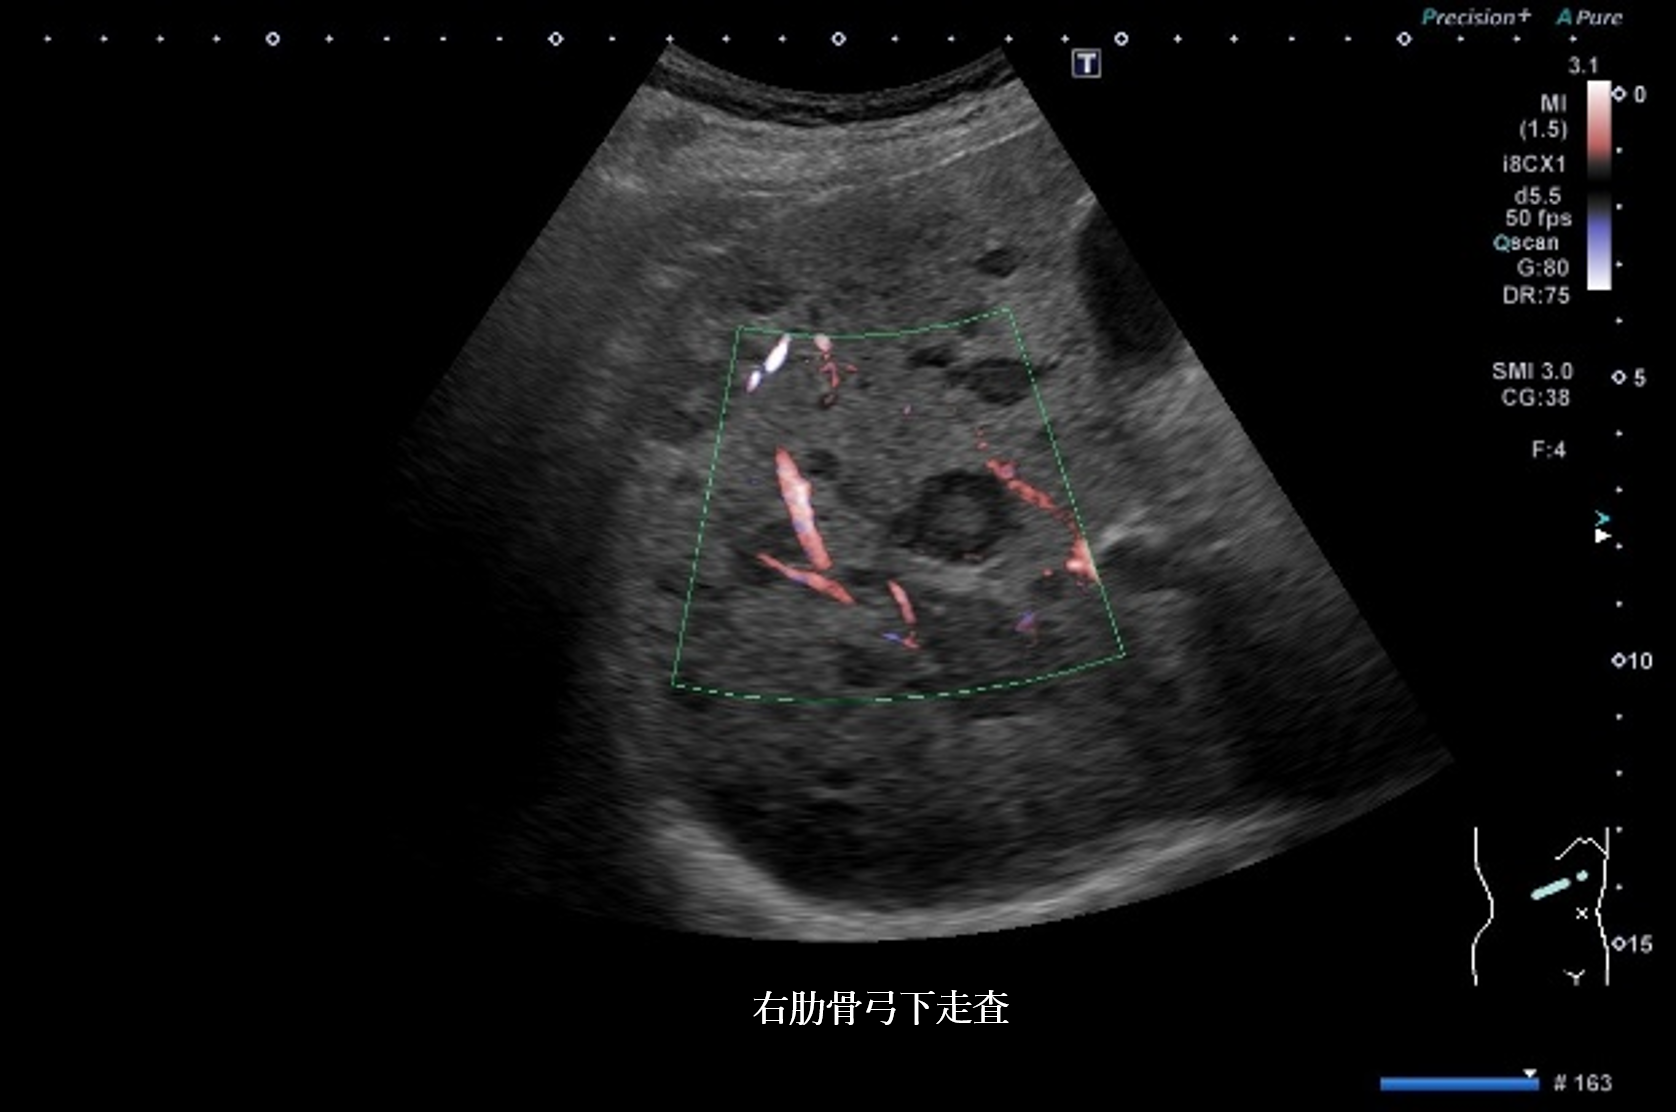

現病歴:肺気腫、間質性肺炎により当院通院中。CT検査を施行したところ、右上葉肺腫瘤を指摘された。

その後右上葉原発小細胞肺癌と診断され、多発脳転移も指摘された。

他臓器転移の有無を確認するため、腹部超音波検査を施行した。

超音波所見より正しいのはどれか

① 肝全体に内部無エコーな腫瘤性病変を多数認める

② 肝全体に腫瘤性病変が多数みられ、辺縁低エコー帯を認める

③ 肝実質は粗雑不均質に観察され、明らかな腫瘤性病変は指摘できない

④ 肝全体に腫瘤性病変が多数みられ、腫瘤内部はモザイクパターンを呈する

⑤ 肝全体に腫瘤性病変が多数みられ、腫瘤辺縁にリング状高エコー像を認める

④ bull’s eye pattern ― 転移性肝腫瘍